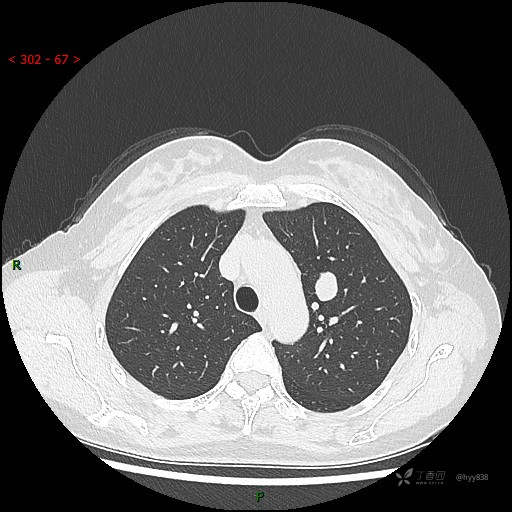

增强动脉期